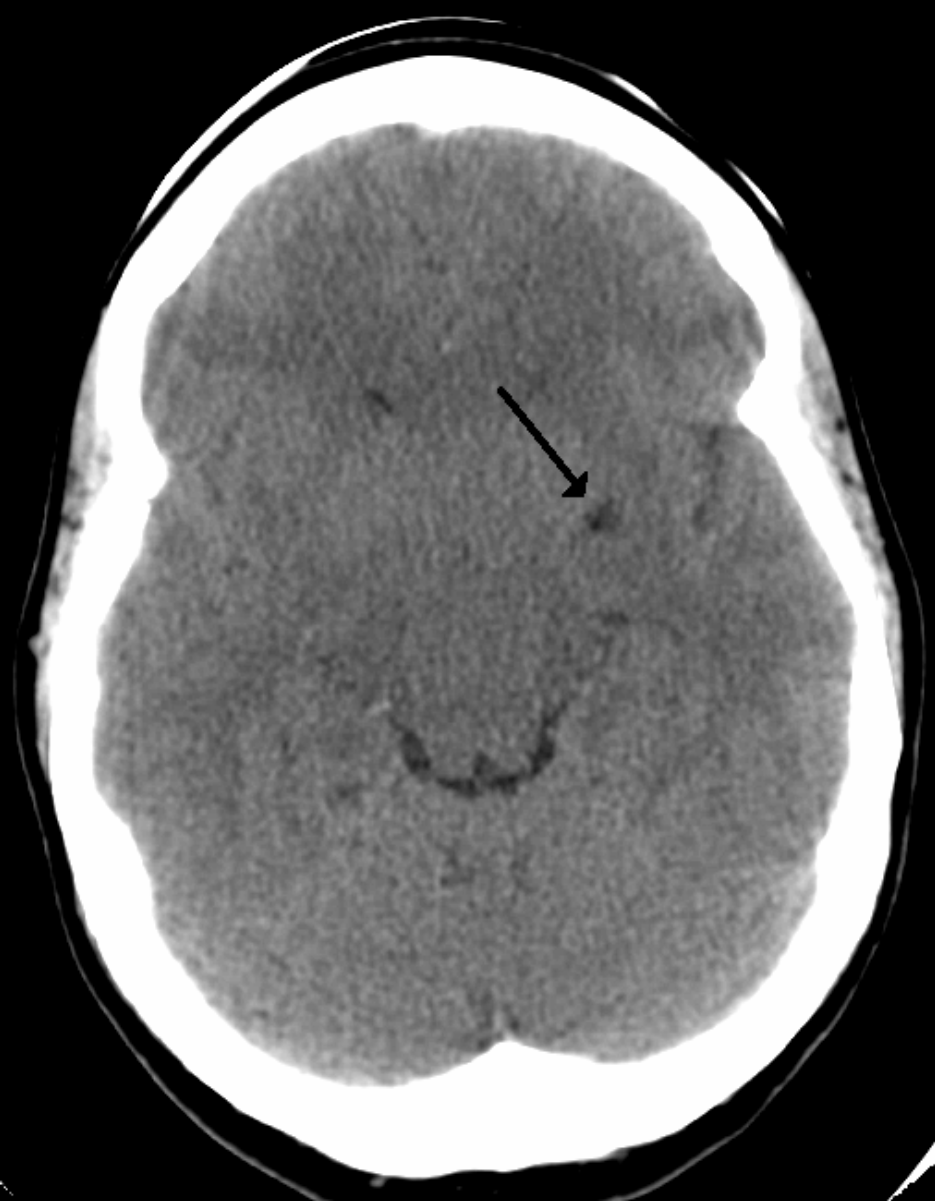

Периваскулярные пространства базальных ядер